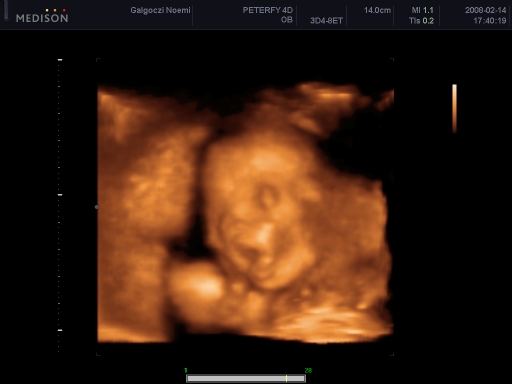

4 D-s ultrahang

Tegnap voltunk! Szuper volt, bár igaz, hogy csúszás volt, de vittem könyvet Bencének, és egész jól bírta!

Szóval:Csillához hasonlóan nekem is az AFP miatt kellett mennem, és tökéletesen egészséges. Borzasztóan ficánkolt! Bence pedig ott fekhetett mellettem, és együtt néztük! :)

Csak 2 D-n mutatta a kukiját, a másikon összezárta a lábát.

Boxolt, ivott a magzatvízből, pisilt, ásított, de szemből nem akarta megmutatni az arcát, mindig odakapta a kis kezét. Súlya: 356 g, fejecskéje 18 cm körben, pocija 15, combcsontja 3,3, ha jól emlékszem!

Összesen 27 db fényképet csináltak cd-n, ebből 1-et kaptunk nyomtatva is, és az egészről kaptunk egy dvd-t, ami 25-30 perc.

Kép

Itt a pofija látszik, a két keze, és bal oldalon felül a jobb talpacskája a feje tetején.

Levi ásít

Az egyik keze az álla alatt, a másikkal fogja a fejét

Olyan, mintha az alsón nem lenne orra! Én parázok egy kicsit, de állítólag csak valami árnyék miatt látszik így, és biztos kiszúrták volna!